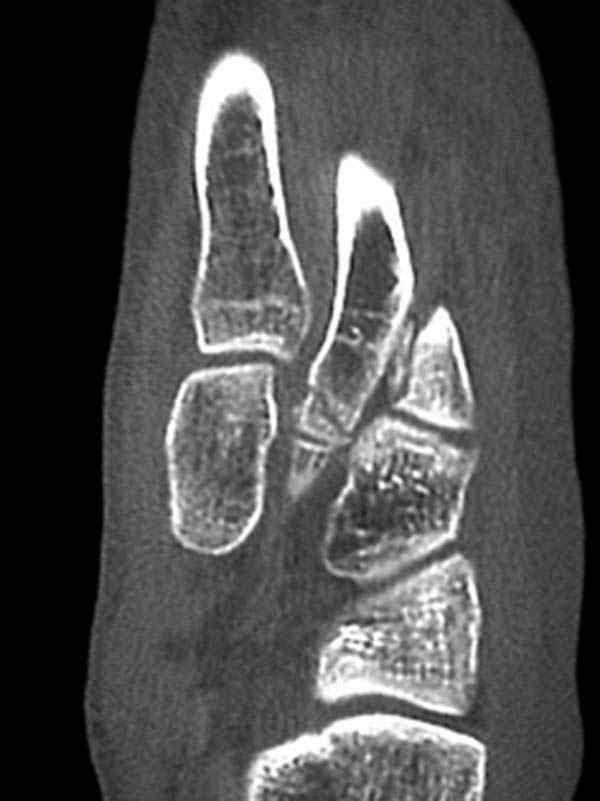

Имя     : CT 2.jpg

Тип     : image/jpeg

Размер  : 38908 байтов

Описание: отсутствует

Url     : http://weborto.net:8080/pipermail/ortho/attachments/20080320/e19da97a/attachment-0004.jpg